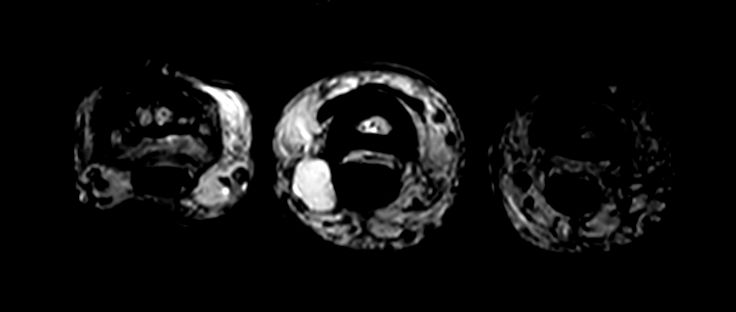

Patient with a ganglion in his finger. dS Microscopy coil set is used, consisting of two 47 mm coils, for small field-of-view imaging with high in-slice spatial resolution and a high signal-to-noise ratio. Compressed SENSE is used in all sequences to shorten the overall exam time for the patient.

Axial T2w TSECompressed SENSE